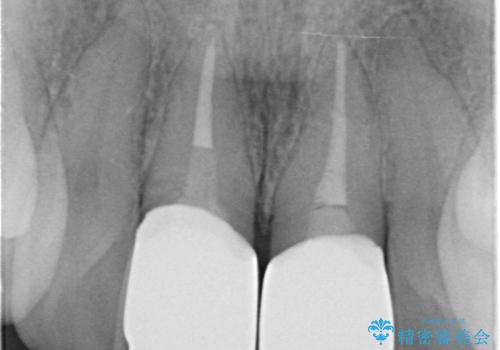

- 前歯の変色を主訴に来院されました。

変色に対してはかぶせ物で周囲の歯との色調を合わせます。

根管治療についてご説明をし、右上の1本だけ再根管治療を行うこととなりました。